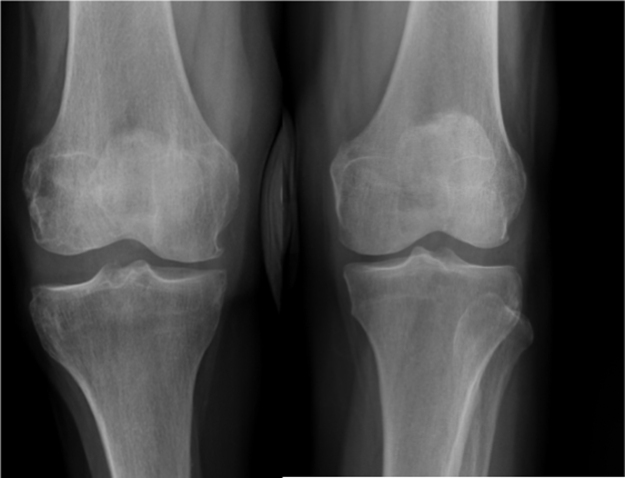

The mean Musculoskeletal Tumor Society score in patients without peroneal nerve resection was 96% (range, 70–100%), while that in patients with peroneal nerve resection was 65% (range, 60–70%). Permanent peroneal nerve palsy, despite nerve preservation, occurred in 1 of 10 patients. Deep venous thrombosis (1/12) also occurred in the same patient during a period of bed rest following neurolysis; therefore, anticoagulant therapy was required. Three patients with postoperative peroneal nerve palsy required foot orthoses. No patients complained of knee instability; however, among patients who were treated without ligamentous reconstruction, 1 patient exhibited knee varus instability when compared with the unaffected side on a varus stress test (Fig. 2).

Fig. 2.

X-ray film of the varus stress test at the last follow-up in 1 fibular head tumor patient who was treated by fibular head resection without reconstruction. Varus instability was detected in the right knee (side on which the operation was performed) in comparison with the healthy side.

The necessity of reconstructing the LCL after tumor excision is controversial because other knee stabilizers, such as the anterior cruciate ligament or posterior cruciate ligament, are intact following surgery for proximal fibular tumors. In this study, 4 patients without LCL reconstruction did not exhibit any knee instability. Einoder et al. also reported good function after fibular head resection without ligamentous reconstruction in 6 patients [7]. However, in this study, 1 patient exhibited instability on a varus stress test (Fig. 1). In contrast, Abdel et al. reported no long-term knee instability with repair of LCL in 112 patients with aggressive benign tumors and 53 patients with malignant fibular tumors [5], [8]. They assessed knee instability using the varus stress test at 30° knee flexion. Therefore, if possible, LCL reconstruction should be considered after fibular head resection, especially in young patients.